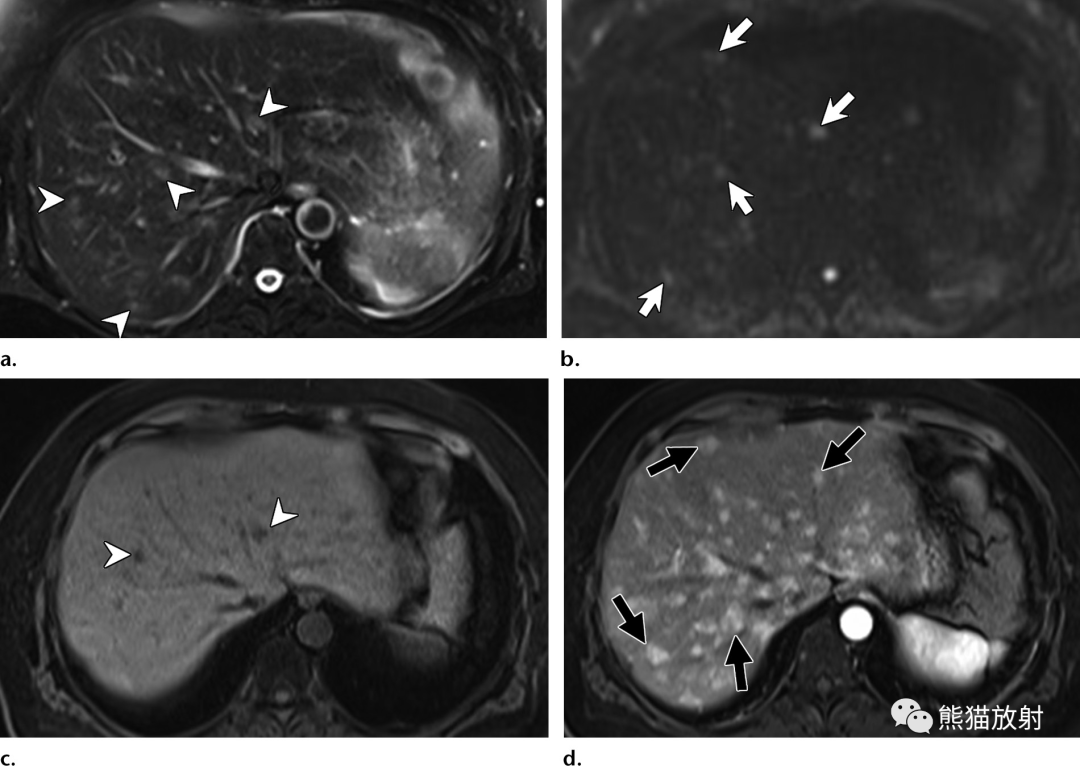

图片

32岁 HIV/AIDS男性患者,细菌性紫癜,表现为发热。

(a)T1WI同相位图像显示肝右叶后段边界不清的等至轻度低信号结节(箭)。(b)脂肪饱和T2WI显示结节呈中高信号(箭),后方肝被膜下见数个较小结节(箭头)。(c)增强动脉早期图像显示结节周围不规则明显强化。(d)增强延迟期结节内部延迟强化,由于造影剂滞留在病灶内扩张的肝窦内,因此达到与周围肝静脉结构相似的信号强度。